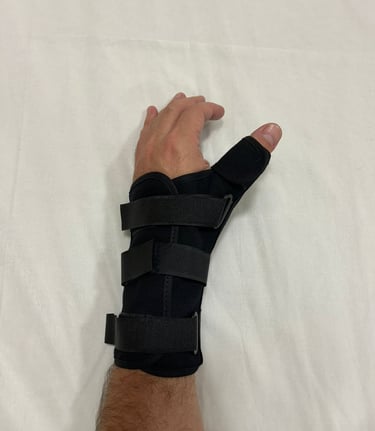

Fraturas e Luxações

Podem ocorrer na mão, punho ou antebraço por acidentes de trânsito, trabalho ou quedas. As mais comuns afetam os ossos da mão (metacarpos), dos dedos (falanges), antebraço (rádio e ulna) e punho (carpo).

O diagnóstico é feito com exames de imagem e avaliação clínica.

O tratamento pode ser conservador ou cirúrgico, conforme o tipo e a gravidade da lesão.